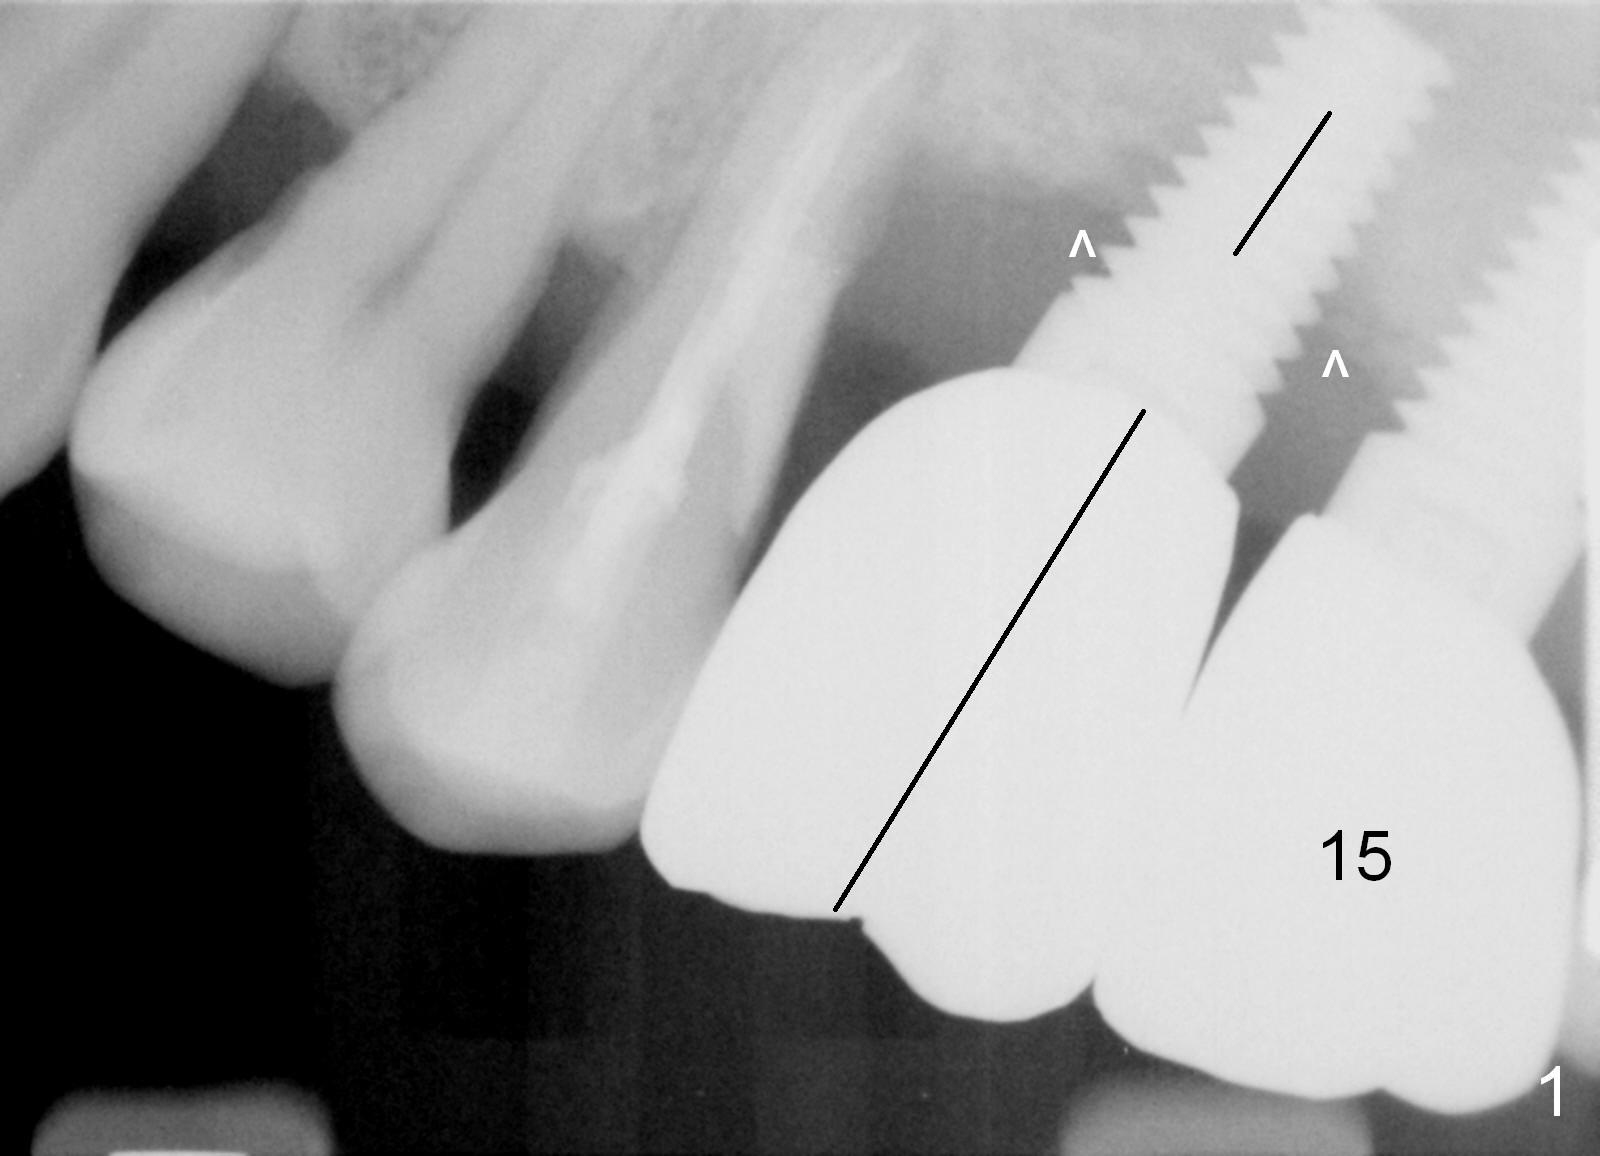

Three months post cementation, the crown at #14 is found to have mobility I with mild tenderness and bone loss (Fig.1,2 ^). The crown/implant ratio is unfavorable (Fig.1). The 1st option of treatment is to remove the crown and the unipost and place a healing screw if the gingiva is healthy. If the implant is fatally loose, remove it, explorer the osteotomy for wall integrity. If it is solid, place 5.5 or 6.0 mm tap (Fig.3) before placing an appropriate implant (e.g., 6x6 mm; allograft for internal sinus lift and coronally) and healing abutment for more than 6 months (vs. 4 months previously). When the implant seems to have osteointegrated, place a provisional from infraocclusion to ortho-occlusion over time (6 months, progressive loading). When the implant appears to withstand normal loading, fabricate a single-unit crown. If not, remove #15 crown and splint #14 and 15 crowns or #13 and 14 in case the tooth #13 fails (Fig.2 limited bone height).